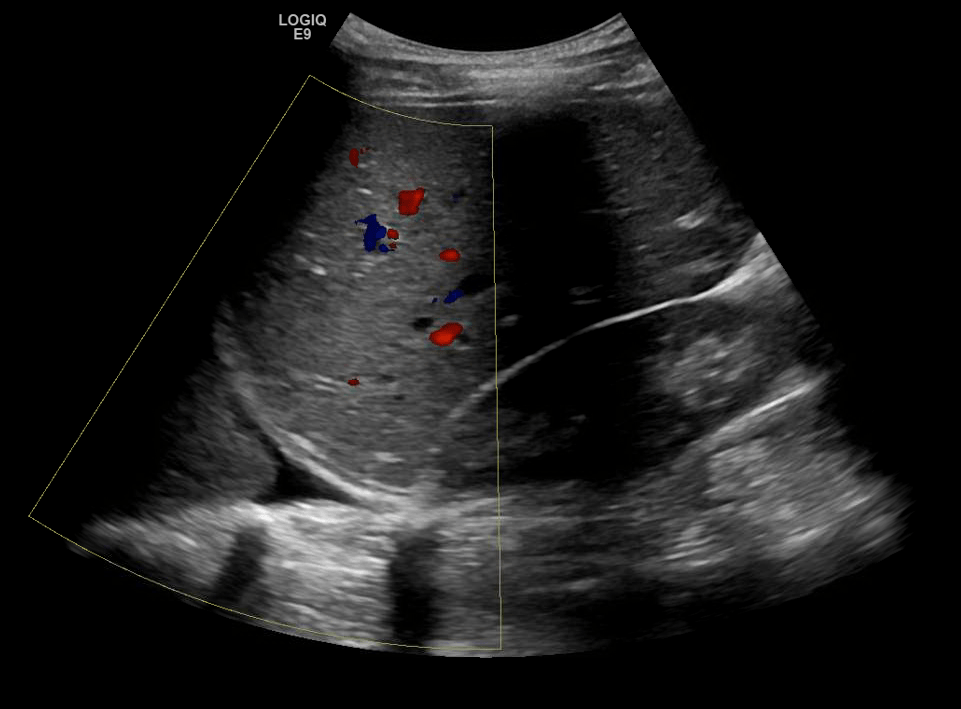

Consolidation

Hepatization of the lung parenchyma due to infiltration with fluid. May also have “air-bronchograms”.

Color doppler will show blood flow through the pulmonary vasculature.

Consolidation/Atelectasis

In alveolar consolidation the lung parenchyma takes on the appearance of liver echotexture, “hepatization”. There may be air bronchograms present in consolidated tissue which appears as hyperechoic air bubbles with reverberation artifacts. Color doppler will show blood flow through the pulmonary vasculature.